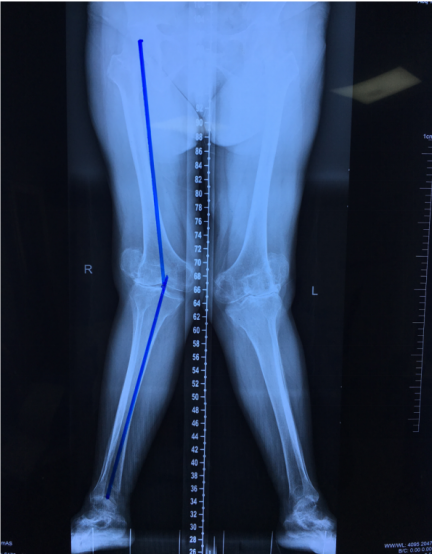

患者女性,82岁,患有双膝疼痛及外翻畸形70余年,主要存在膝关节发育异常,70年来一直不能和常人一样正常行走,膝关节疼痛较轻时,服药治疗会缓解。近15年来双膝疼痛及膝外翻畸形程度逐渐加重,曾就诊过多家三甲医院,都认为手术治疗难度大、风险高采取保守治疗,疗效欠佳,且病情反复,此次入院前3周疼痛再发加重,难以忍受、无法下地行走,再次到当地医院就诊,治疗无效后慕名前来我院就诊。入院后,完善双侧膝关节局部X线、双下肢负重位全长X片、双膝关节CT检查发现:双膝关节重度退行性变,双膝关节间隙重度狭窄,关节周围大量骨赘形成,软骨下骨质硬化,双膝外翻畸形,左膝为重,双膝内外侧关节间隙不对等,关节间隙消失,关节周围大量骨赘形成,双侧髌骨向外侧半脱位,双侧股骨髁部发育不良。

患者术前大体照及影像学资料